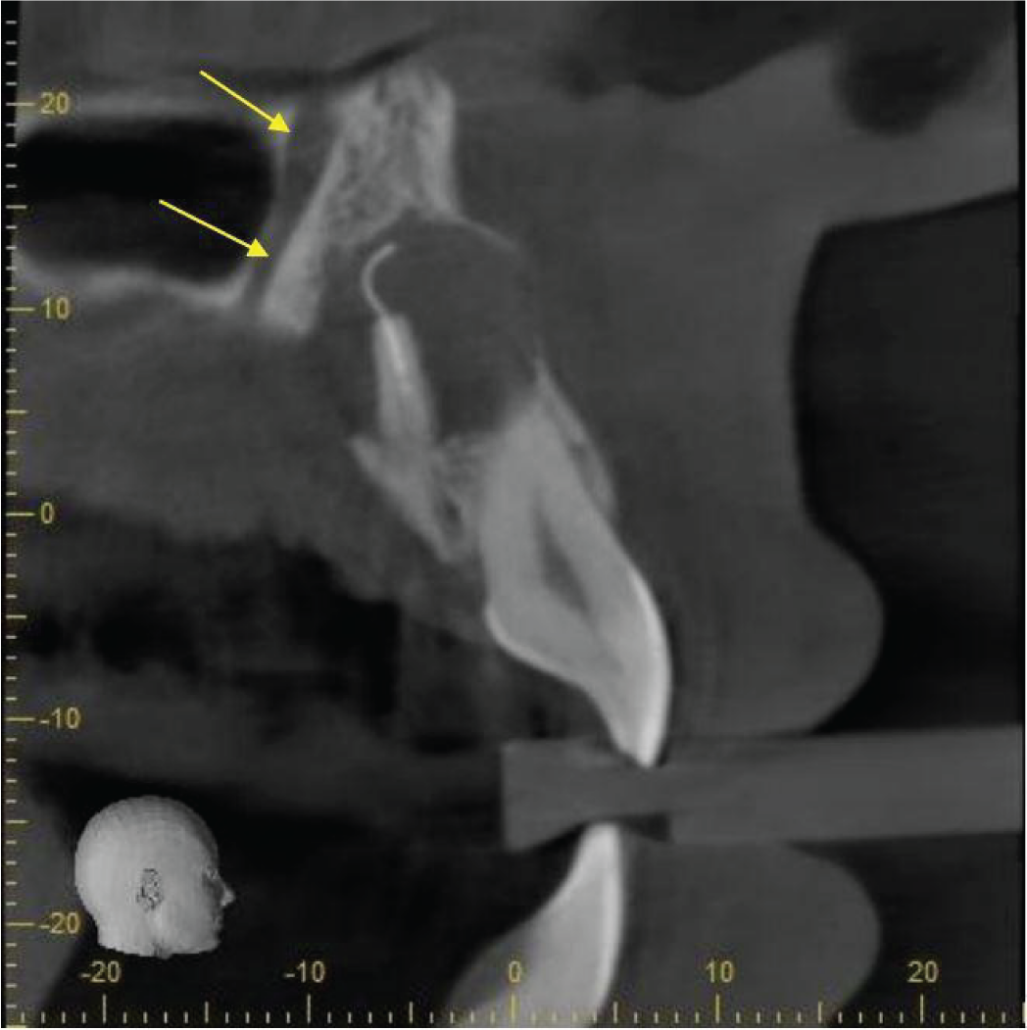

A large terminal branch of the anterior superior dentoalveolar canal runs about 2mm palatal to the lesion along the maxillary antral anterior wall (image 4).

Labio-palatal cross-section to show the prominent neurovascular canal